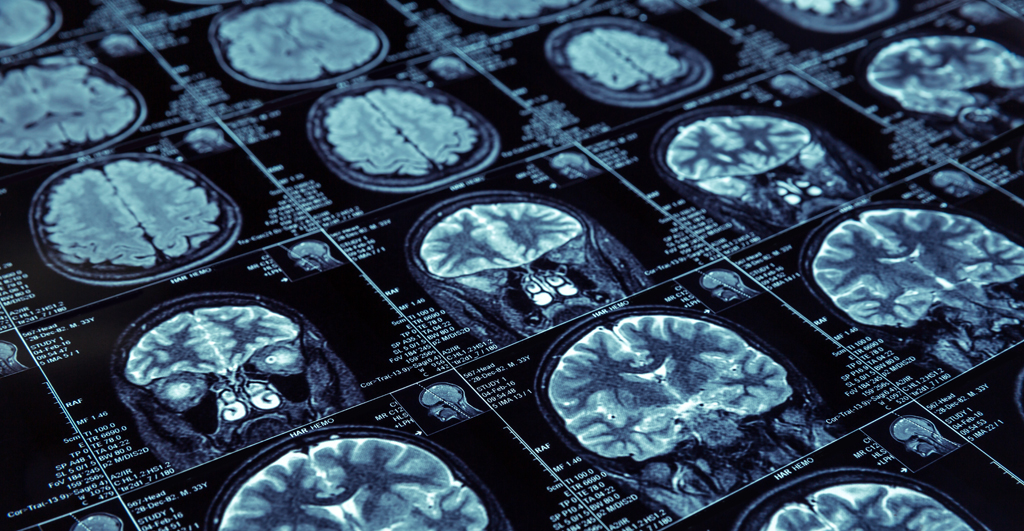

Neben Experimenten zu Kognition und Gleichgewicht gehören EEG- und MRT-Messungen zum experimentellen Teil der Studie. Diese will herausfinden, welche Einflüsse die Haltungskontrolle insbesondere bei älteren Menschen stören können. "Bei Menschen über 65 gibt es einen enormen Anstieg von Stürzen", so die Psychologin. Die Sturzgefahr ist besonders hoch, wenn ältere Personen mehrere Dinge gleichzeitig tun: also beim Multitasking. "Im Alter sind auf verschiedenen Ebenen Prozesse im Abbau. Gleichgewicht, Mobilität und Koordination benötigen mehr Aufmerksamkeit als bei jüngeren Menschen." Zugleich ist auf kognitiver Ebene das Arbeitsgedächtnis stärker herausgefordert. Dieses wird mit dem präfrontalen Cortex an der Stirnseite des Gehirns assoziiert und ist besonders wichtig für die flexible Handlungssteuerung.

Universität Potsdam, Campus Am Neuen Palais, regnerisch, 17° Celsius. Heute findet die Elektroenzephalografie-Messung statt. Eine Dreiviertelstunde benötigen die zwei Studierenden, um die EEG-Kappe auf meinem Kopf zu installieren und dabei die elektrische Spannung an jeder Ableitstelle unter fünf Kilo-Ohm zu bringen. Wenn ich schlucke, blinzle oder spreche, schlagen die Messkurven der elektrischen Strömung in meinem Kopf aus; ich kann sie auf einem vor mir liegenden Tablet-PC verfolgen. Dann geht es los. Wieder gilt es, auf angezeigte Quadrate und Töne mit Tastendruck oder einem "Ja" zu reagieren. Anders als beim ersten Termin mache ich diese Übung zuerst entspannt im Sitzen und anschließend auf einer Kraftmessplatte im Tandemstand, bei dem der linke Fuß etwas weiter vorn steht und beide Füße sich berühren. Auch für mich gilt: Nicht aus dem Gleichgewicht kommen! Während die Studentin die Übungen auf dem Desktop koordiniert, beobachtet ihr Kommilitone mein Gleichgewicht auf der Kraftmessplatte. Das EEG zeichnet derweil auf, wie mein Gehirn diese Aufgaben reguliert. Nach rund drei Stunden Training für Körper und Geist sind ausreichend Daten gesammelt.

"Wir wissen, dass das Arbeitsgedächtnis auch bei älteren Menschen trainierbar ist", sagt Stelzel. Daher nehmen die älteren Probanden im Anschluss an die Studie an einem Training teil, bei dem sie Gleichgewicht und Kognition gleichzeitig üben. "Mit den neurowissenschaftlichen Parametern aus dem EEG und dem MRT hoffen wir, vorhersagen zu können, welche kognitiven Aufgaben das Gleichgewicht stören", erläutert die Psychologin. Während Stelzel die Auswertung des MRT übernimmt, fokussiert Gesche Schauenburg die Datensätze der EEG-Messung. Die Kraftmessplatte, auf der die Probanden stehen, misst kontinuierlich den Kraftangriffspunkt der beiden Füße auf der Platte. Sie zeichnet genau auf, wenn der Proband schwankt. Die Forscher nehmen einen Zusammenhang zwischen dem Schwanken und der Schwierigkeit der kognitiven Aufgabe an. Multitasking ist aber für niemanden leicht. Manche Theorien gehen sogar davon aus, dass es prinzipiell nicht möglich ist, mehrere Dinge gleichzeitig zu tun: Zwar kann man mehrere Reize aufnehmen, doch um zu entscheiden, wie man darauf reagiert, muss man eine Aufgabe unterbrechen - zumindest ganz kurz.

Berlin Center for Advanced Neuroimaging Charité, 25° Celsius, sonnig. Der letzte Teil der Studie steht bevor: In der Berliner Charité löse ich Aufgaben im Magnetresonanztomografen (MRT). Zunächst erklärt mir eine Mitarbeiterin das Vorgehen: Ich darf kein Metall am oder im Körper tragen, die Schuhe muss ich ausziehen. Wenn etwas nicht in Ordnung ist, kann ich einen Notfallknopf drücken, denn wer unter Platzangst leidet, fühlt sich in der Röhre nicht wohl. Den Kopf darf ich während der Untersuchung nicht bewegen, er wird mit zwei Polstern stabilisiert. Über meinem Kopf befindet sich ein Bildschirm, der die Übungen zeigt. Stelzel und ihre Kollegin können mich im Tomografen während der Aufgaben nicht hören. Nur in den Pausen kommunizieren wir über eine Sprechanlage. Im MRT ist es laut, deswegen erhalte ich Ohrstöpsel und schalldämpfende Kopfhörer. Die brauche ich auch, denn ich soll einen "Zielton" und ein "Zielquadrat" wiedererkennen und mit Tastendruck bestätigen. Anschließend folgen erneut viele Durchgänge der Ton-Quadrat-Aufgabe - anderthalb Stunden liege ich still in der Röhre. Wieder draußen: Meine Finger sind etwas kalt geworden, die Beine leicht eingeschlafen, der Nacken ist etwas verspannt. Ansonsten fühle ich mich gut. Zum Abschied erhalte ich noch ein Bild meines Gehirns aus dem MRT.

"Die funktionelle Magnetresonanztomografie ist eine räumlich gut auflösende Methode", erklärt mir Christine Stelzel. "Sie stellt den Sauerstoffverbrauch im Gehirn dar und damit Aktivitätsveränderungen in den einzelnen Hirnregionen." Denn wenn eine Aufgabe besonders schwierig ist, benötigt ein Areal viel Sauerstoff. Das EEG dagegen sei eine zeitlich hochauflösende Methode, die elektrische Veränderungen in Millisekunden aufzeichne. Die beiden Methoden können also die Schwierigkeit der Aufgaben sichtbar machen. Das MRT zeigt jedoch auch die sogenannte Konnektivität zwischen den Gehirnregionen an und macht damit sichtbar, welche Areale bei welchen Aufgaben zusammenarbeiten. Am Ende wollen die Forscher beide Datensätze für jeden Probanden zusammenbringen. Denkbar wäre, dass besonders schwierige Aufgaben zu auffälligen Ausschlägen der elektrischen Spannung (EEG) und hoher Aktivität in bestimmten Gehirnarealen (MRT) sowie zu einem verstärkten Schwanken auf der Kraftmessplatte geführt haben. Daraus könnte sich ableiten lassen, welche kognitiven Aufgaben das Gleichgewicht stören. Und es ließe sich ein passendes Trainingsprogramm (ein sogenanntes "Multitask Gleichgewichtstraining") entwickeln, das letztendlich das Risiko eines Sturzes senken würde.